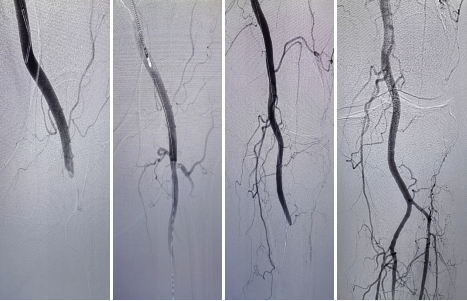

醫務科(kē)立即組織相(xiàng)關科(kē)室進行術(shù)前討(tǎo)論,當晚急診行“下肢動脈造影(yǐng)+經導管血栓清除術(shù)”,使用Straub血栓抽吸術(shù),通過Rotarex導管頭端的高速旋轉,擊碎血栓栓塞物質并吸出體(tǐ)外。

這種新技術(shù)隻需要通過微創開展,無需開刀。與導管溶栓相(xiàng)比,這些吸栓和切栓系統能夠更快(kuài)地複通血管。

手術(shù)曆時1小時,取出大(dà)量血栓,劉某左下肢血流恢複,皮溫回升,疼痛消失。次日(rì)即可(kě)下床活動,恢複同前。